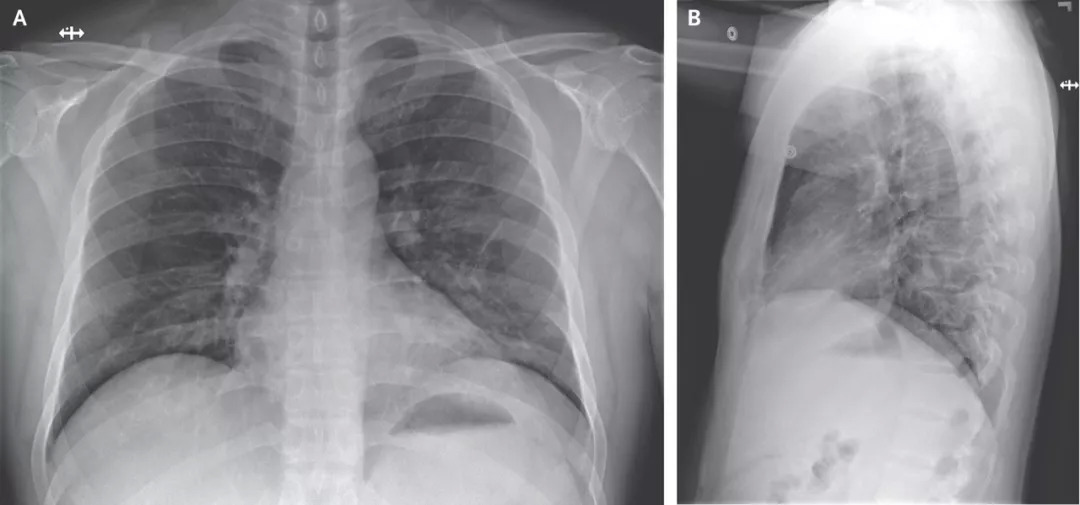

在医院第3天拍摄的胸部X光片未显示浸润或异常迹象(图三)。但是,从医院第5天晚上晚上进行的第二次胸部X光片显示,左肺下叶有肺炎的迹象(图四)。

图三